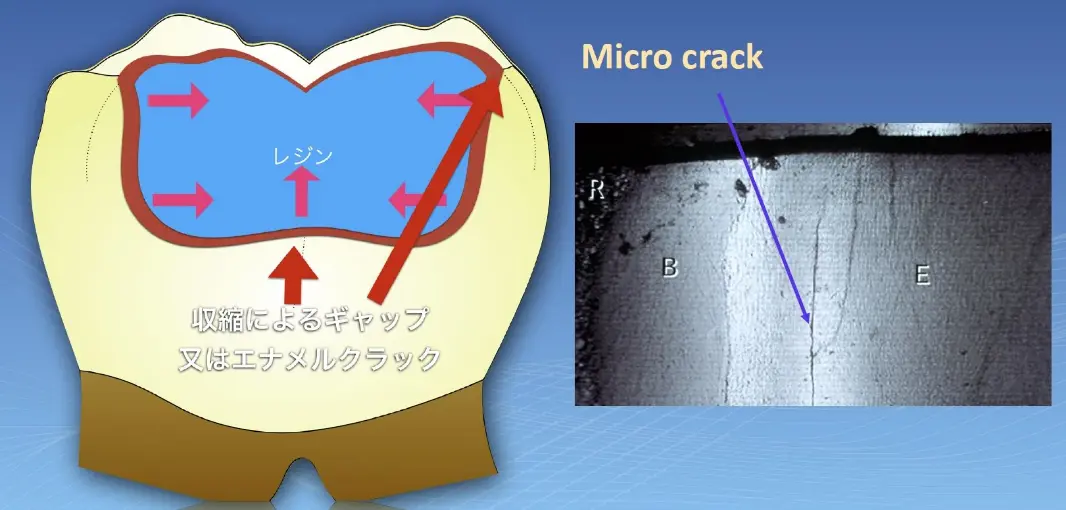

実は、保険適用の白い樹脂(レジン治療)も2mmを超える虫歯に使うとトラブルになってしまいます。

その理由は、レジン*1を最後に光で固める際に収集が起き、隙間*2を埋めようとレジンに健康な歯*3が引っ張られてひびが入ってしまうためです。

ひびが入ることにより、歯の痛みや知覚過敏が起きて2次被害がでてしまいます。

*1:図解中のR

*2:図解中のB(ボンディングの頭文字)

*3:図解中のE(エナメル質の頭文字)